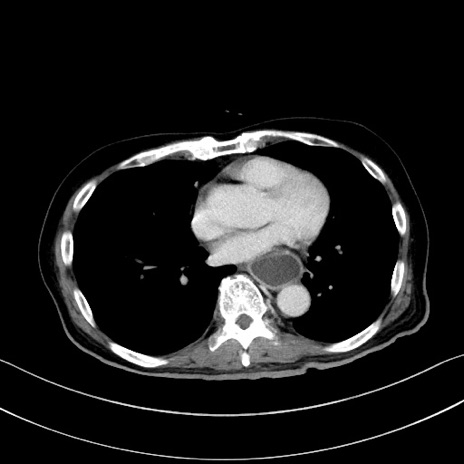

症例28(横断像)

【症例】60歳代男性

【主訴】嘔吐

【現病歴】胃癌にて胃全摘後。食思不振が悪化し、夜中に嘔吐することがある。

【既往歴】胃癌、胃全摘、脾摘、胆摘後

【データ】WBC 5900、CRP 10.56